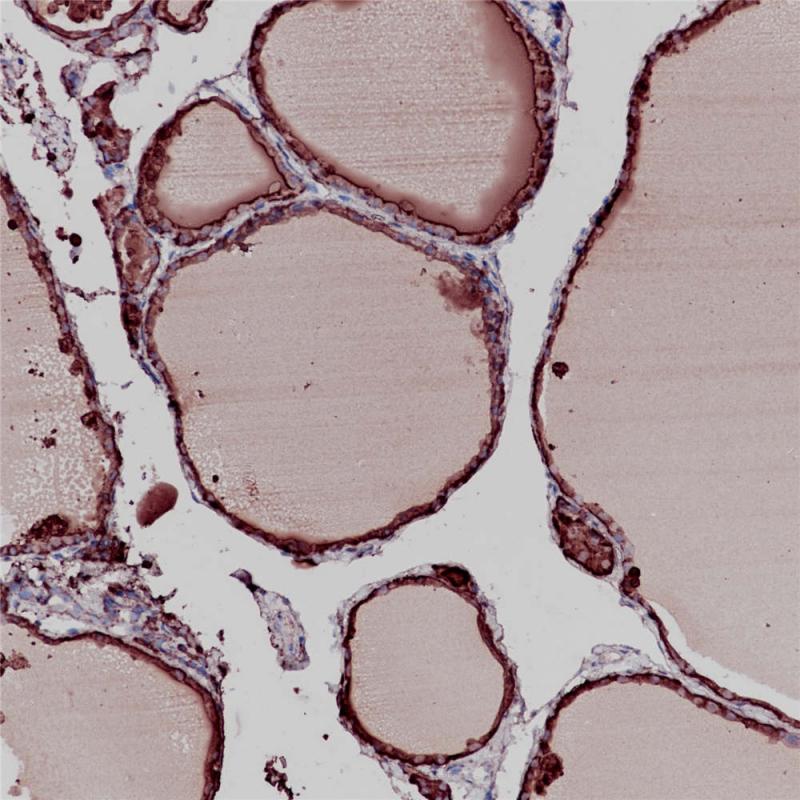

Thyroglobulin(TG)是一种在甲状腺特异性表达的二聚体糖蛋白,属于B型羧酸酯酶家族。它是甲状腺激素T3与T4的前体。TG的变化通常与3型自身免疫性甲状腺疾病相关。TG合成缺陷通常会导致先天性甲状腺功能低下。甲状腺中TG的缺失和碘清蛋白浓度的上升,最终导致T3和T4的合成障碍。甲状腺球蛋白在正常甲状腺组织以及分化的甲状腺癌细胞中表达。这个指标常用来鉴别甲状腺来源的肿瘤。

阳性对照

甲状腺癌